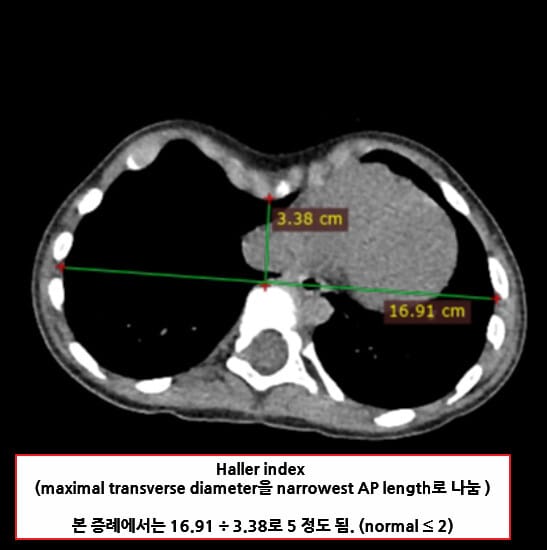

Haller Index

오목가슴증의 정도를 파악합니다.

Chest CT에서 Maximal transverse diameter을 narrowest AP length로 나누어 측정합니다.

- Halar Index ≥ 3.25 이면 수술적 치료를 고려

| 🔵 흉부 CT(Chest CT) 및 Haller Index 측정 |

| 횡격막에서 흉골과 척추 사이의 가장 좁은 거리와 가슴의 가로폭을 이용해 Haller 지수를 계산합니다 (Haller index ≥ 3.25 시 수술 고려). |